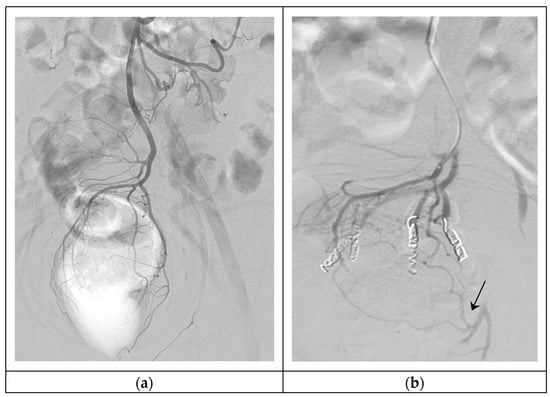

- Ferrer Puchol, M.D.; Esteban Hernández, E.; Blanco González, F.J.; Ramiro Gandia, R.; Solaz Solaz, J.; Pacheco Usmayo, A. Selective intra-arterial embolisation to treat haemorrhoids. Radiología 2020, 62, 313–319. [Google Scholar] [CrossRef]

| Ferrer puchol et al. [28] 2020 | Prospective case series | 20 patients: 18 with chronic pain and bleeding due to HD grade II and III, with contraindications to surgery and 2 needing urgent embolization | 90/83.4 | 300–500-μm PVA Particles and 2–3 mm coils | 1 episode of IMA dissection 3 episodes of rectal heaviness and pain |